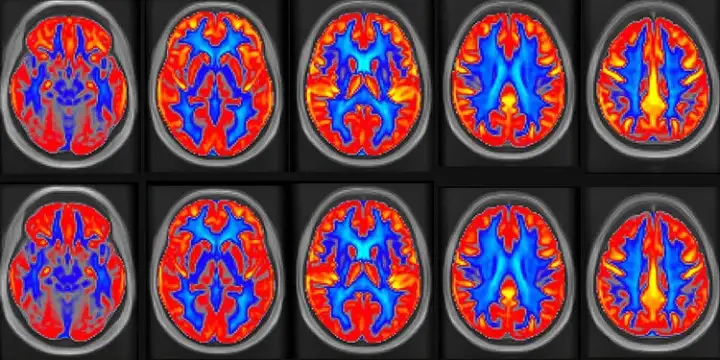

Состояние участников отслеживали при помощи МРТ. Состояние участников отслеживали при помощи МРТ.© Lucia Kerkhof

Визуализация на МРТ показала, что общий мозговой кровоток у пациентов увеличился на 3,6%, а кровоток в сером веществе — на 4,5%. Адекватный кровоток необходим, чтобы мозг быстро получал кислород и питательные вещества, от чего непосредственно зависят такие ключевые функции, как память. Артериальное давление и диета участников также отслеживались с помощью анкет.